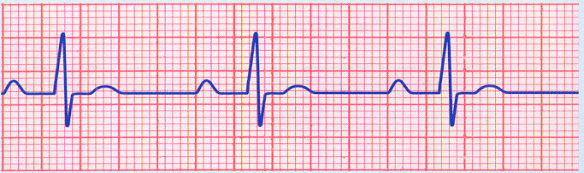

What’s the cause of this rhythm?

1st degree AV block

Q

How do you interpret this rhythm and how do you treat?

A

• 1st degree AV block

• Tx: do nothing